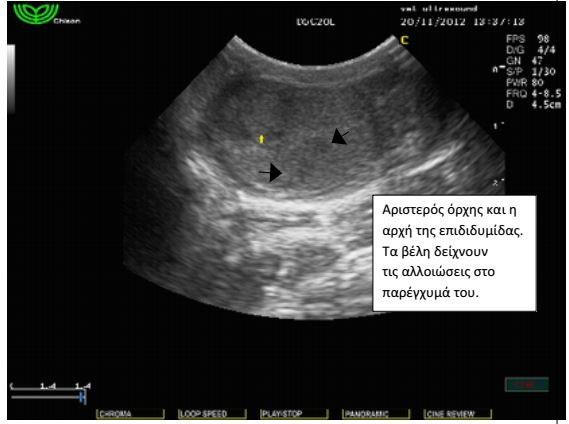

Σε γενική εξέταση αίματος κατά τον ετήσιο προληπτικό έλεγχο βρέθηκε ήπια μείωση του αιματοκρίτη και μέτρια αύξηση των λευκών αιμοσφαιρίων.Έγινε υπέρηχος κοιλίας όπου και διαπιστώθηκε ήπια διόγκωση του προστάτη αδένα. Τα υποσφυικά λεμφογάγγλια δεν βρέθηκαν διογκωμένα. Τα υπόλοιπα όργανα ήταν εντός των φυσιολογικών ορίων και χωρίς απώλεια της φυσιολογικής δομής τους. Στο παρέγχυμα των όρχεων εντοπίστηκαν αλλοιώσεις σαφώς περιγεγραμμένες με υποηχογενή άλω. Το FNB( fineneedlebiopsy) των αλλοιώσεων αποκάλυψε πως πρόκειται για μια νεοπλασματική εξεργασία των όρχεων, το σερτολίωμα. Οι αλλοιώσεις αυτές παράγουν οιστρογόνα και για το λόγο αυτό, μακροπρόθεσμα, μπορούν να προκαλέσουν απλασία του μυελού των οστών και μείωση του αιματοκρίτη. Το περιστατικό αντιμετωπίστηκε με ορχεκτομή. Μετά από λίγους μήνες οι αλλοιώσεις του προστάτη υποχώρησαν και η τιμή του αιματοκρίτη αποκαταστάθηκε στα φυσιολογικά επίπεδα